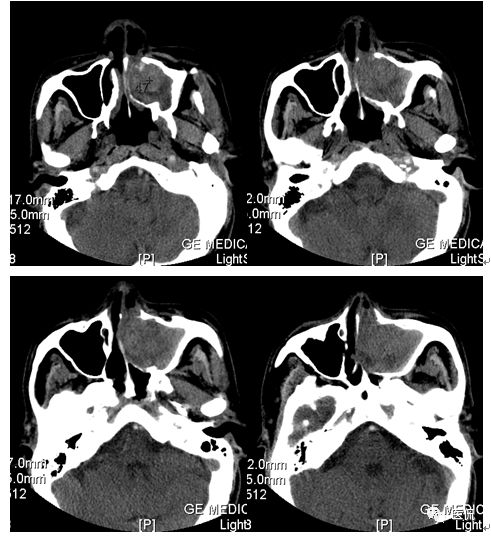

CT平扫及增强示:左侧上颌窦及鼻腔可见软组织密度影,呈膨胀性生长,周围骨质压迫性吸收破坏,累及左眶,病灶密度不均匀,周边区可见点状钙化,增动脉期轻度强化,局部见小灶性稍高密度区,静脉期病灶内见不均匀明显强化,CT值最高达117HU,延迟期强化范围有所增大。

影像学表现呈软组织密度,多不均匀,表现为高低混杂密度,病变窦腔内息肉、血肿、坏死、感染共存,是病灶密度不均匀的主要原因,息肉反复出血、血管机化亦为其成因之一。病灶内钙化,可为团块状或小片状,可能为病变组织坏死后钙质沉着所致。由于病变组织内有大量炎性细胞浸润和丰富的毛细血管,增强后常有强化。有文献报道病灶增强中心区强化不明显,外周呈轻度强化,推测病灶内虽然血管丰富,但中心区容易出现血流动力学障碍,血管内常有血栓形成,中心区易发生出血坏死,另外,可能与增强扫描延迟时间选择不当有关。

本例病灶较大,周围骨质可见吸收破坏,并累及眼眶,病灶内少量钙化,增强扫描具有一定特征性,表现为动脉期轻度强化,局部见小灶性稍高密度区,静脉期病灶局部呈明显强化,CT值最高达117HU,延迟期强化范围有所增大,呈延迟渐进性强化的特点,推测为病灶内出血所致。